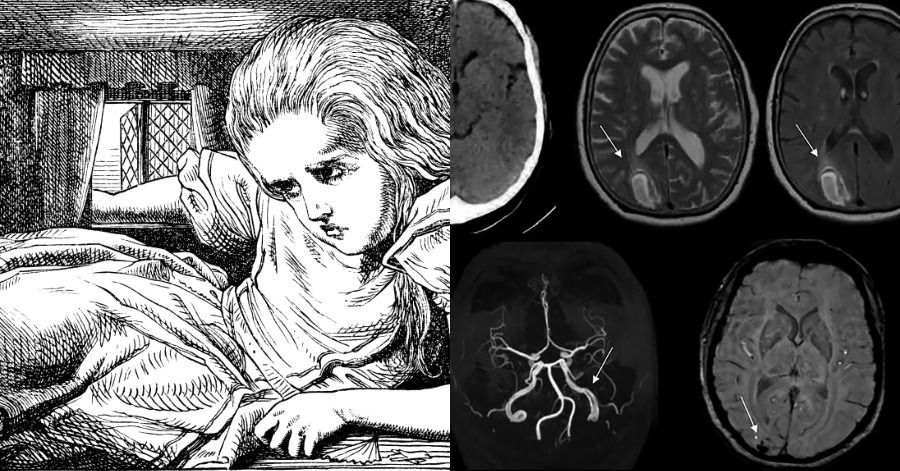

Alice in wonderland syndrome (AIWS) describes a set of symptoms with alteration of body image. An alteration of visual perception is found in that way that the sizes of body parts or sizes of external objects are perceived incorrectly. The most common perceptions are at night.